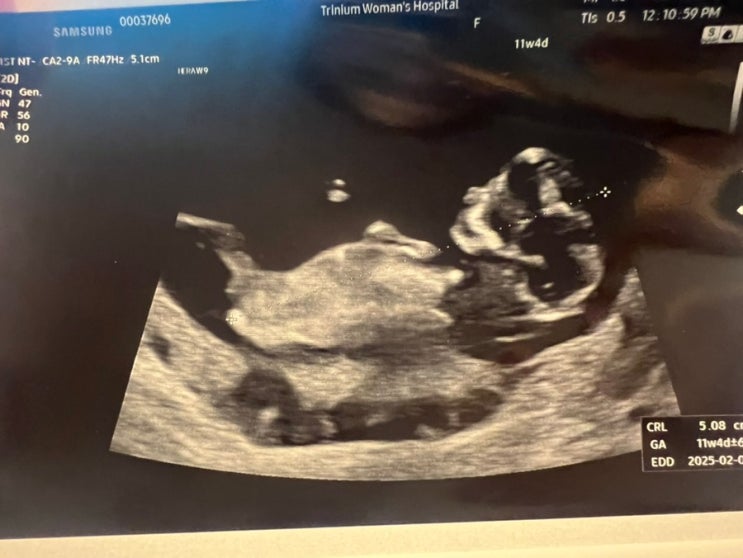

임신)11주차증상 (11주차0일, 11주차1일, 11주차2일, 11주차3일, 11주차4일, 11주차5일)

체력이 굉장히 후달렸던 11주 후기입니다 [2024-07-18] 11주차 0일 지금은 21:14분 ... 글을 쓰고 있는 와...